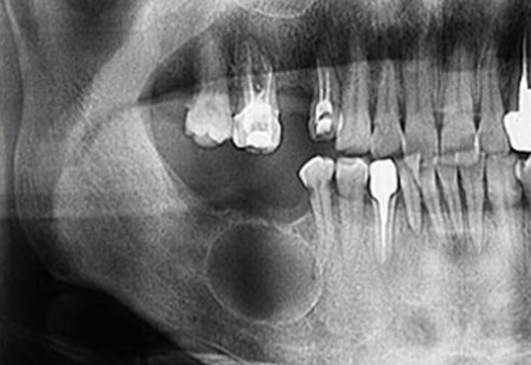

Киста корня зуба на ортопантомограмме

Развернутую информацию стоматологу предоставляет ортопантомограмма. Нередко выявляется киста корня зуба на панорамном снимке, выполненном перед протезированием для оценки состояния всей зубочелюстной системы. Иногда при таком обследовании выявляется несколько образований.

Результаты рентгенографии изучает врач, который будет проводить лечение. Но многие пациенты желают знать, как выглядит киста зуба на снимке, чтобы убедиться в наличие образования. Капсула с гнойным содержимым имеет вид темного пятна на фоне светлых десневых тканей, зубных корней. На изображении можно определить контур кисты, оценить ее размеры.

Специалист определяет не только параметры. Образование в межкорневом пространстве, в десневой ткани, киста корня зуба на рентгене позволяют выявить причину появления. При проникновении инфекции из кровотока, вследствие пульпита, периодонтита формируется радикулярное образование. Резидуальная форма появляется из-за попадания болезнетворных микробов после удаления зуба.